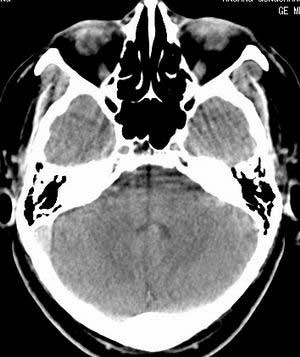

脑实质密度均匀,未见异常密度灶,脑沟裂池室形态大小正常,中线结构居中.

双侧乳突蜂房密度呈气体样,慢性乳突炎可能性不大,

双侧颞叶脑实质密度均匀未见异常密度灶,

考虑颅内未见异常。